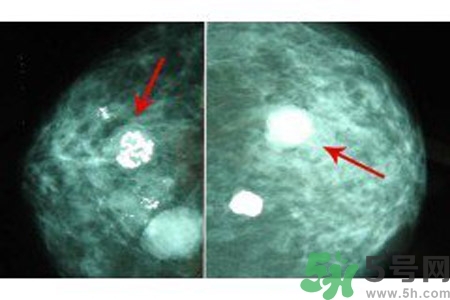

乳腺增生鈣化是乳腺癌常見(jiàn)的影像學(xué)表現(xiàn)之一。某些特異形態(tài)的乳腺增生鈣化是乳腺癌的危險(xiǎn)因素,統(tǒng)計(jì)資料表明65%的乳腺癌有鈣化,其中70%為惡性鈣化。

早期乳腺癌唯一的X線征象

成簇樣微小鈣化常是早期乳腺癌唯一的X線征象。根據(jù)微小鈣化形態(tài)、大小、數(shù)量和密集度等表現(xiàn)可反映病變性質(zhì)和范圍。微小鈣化點(diǎn)可位于腫塊內(nèi)或周圍,總數(shù)目6~15枚,密度不均,大小不等。

乳腺X線檢查可提高隱匿癌、微小癌(直徑小于10mm)和早期癌的診斷率。直徑小于10mm腫塊定性困難,但細(xì)沙型鈣化常是惡性病變的警報(bào);若同時(shí)出現(xiàn)周圍結(jié)構(gòu)紊亂,雙側(cè)不對(duì)稱,血管影增粗等征象則惡性病變可能性更大。

良性惡性乳腺增生鈣化的差異

與良性乳腺增生鈣化相比,惡性乳腺增生鈣化群平均密度較低,密度及大小對(duì)乳腺疾病良惡性鑒別價(jià)值較大。乳腺X線片中微小鈣化分布似乎無(wú)規(guī)律可循,但病理發(fā)現(xiàn)癌腫發(fā)生于末梢導(dǎo)管時(shí),鈣化可位于大片壞死組織中或癌細(xì)胞間,亦可存在于所屬上級(jí)導(dǎo)管內(nèi)或?qū)Ч芊植嫣幓蛳噜徬倥萸粌?nèi)。